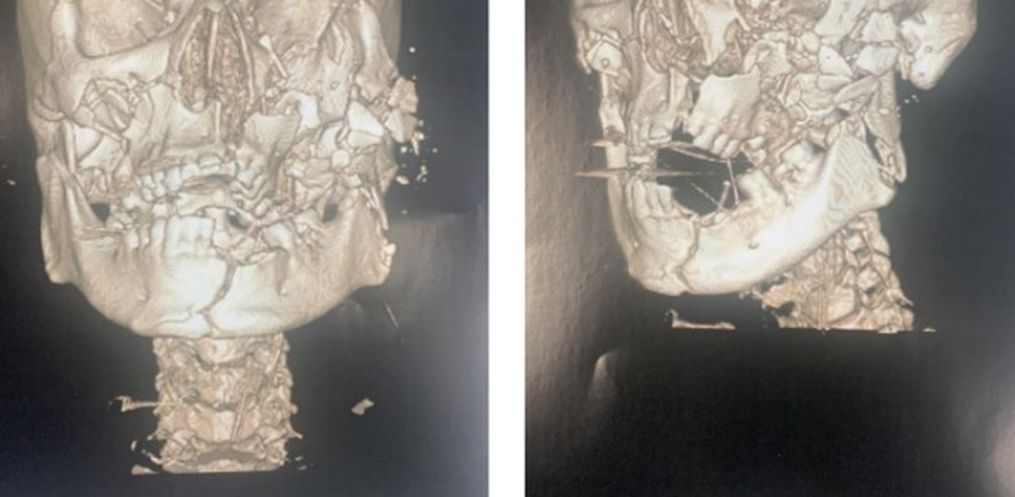

A Polícia Civil de Santa Catarina, por meio da Delegacia de Polícia de Cunha Porã, concluiu na última segunda-feira, 16, o Inquérito Policial que investiga um grave crime de tentativa de homicídio ocorrido em Cunha Porã na madrugada do dia 26 de dezembro do ano passado, ocasião em que um homem foi encontrado por moradores com múltiplas fraturas no rosto e crânio provocados por golpes de arma branca (facão).

Diante da gravidade das lesões sofridas pela vítima, ela somente foi identificada no dia seguinte, por meio de uma tatuagem no seu peito, pois estava com o rosto completamente desfigurado e não possuia documentos de identificação.